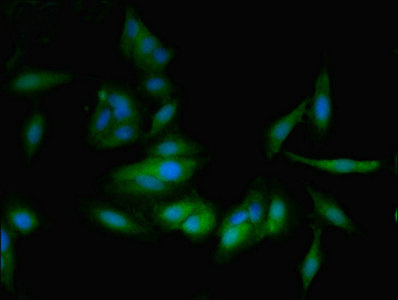

應用范圍:ELISA, IHC, IF

Application Recommended Dilution IHC 1:20-1:200 IF 1:50-1:200 -

亞細胞定位:Rough endoplasmic reticulum. Nucleus membrane. Golgi apparatus. Cytoplasm, perinuclear region. Secreted. Note=Detected on rough endoplasmic reticulum of arachnoid and menigioma cells. Localized to the nuclear envelope, Golgi apparatus, secretory vesicles and spherical cytoplasmic structures in arachnoid trabecular cells, and to circular cytoplasmic structures in meningeal macrophages and perivascular microglial cells. In oligodendrocytes, localized to the rough endoplasmic reticulum and nuclear envelope. In retinal pigment epithelial cells, localized to distinct cytoplasmic domains including the perinuclear region. Also secreted.